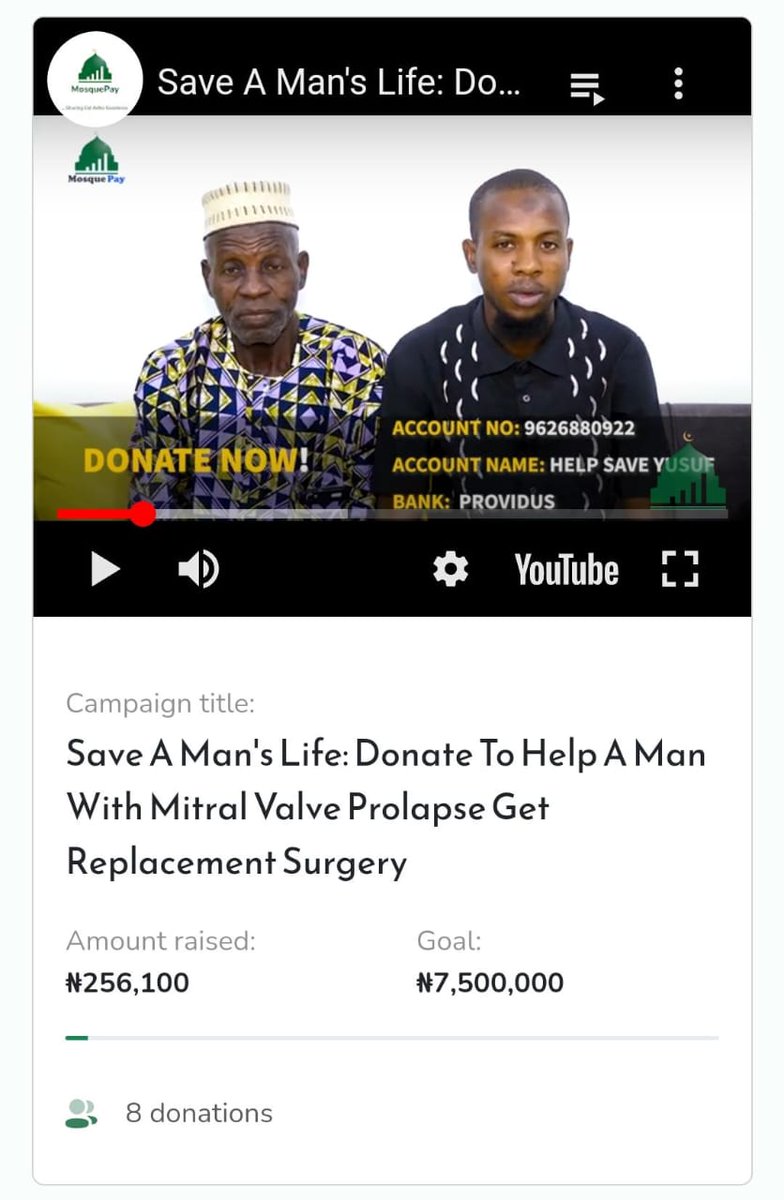

Alhamdulillah We have raised: ₦2,758,900 Pending fund: ₦4,741,100 Goal: ₦7,500,000 Updated On: 1/10/2023 Days Left to raise funds: 19 days Please, nothing is too little to help him get his life back. #saveyusuf Account Number: 9626880922 Bank Name: Providus Bank Account…

He was diagnosed with anterior mitral valve prolapse with severe mitral regurgitation, dilated right ventricle, pulmonary hypertension, and persistent left superior/vena cava, which has seen him wreaking havoc with pain and running from pillar to pole to raise the funds

Alhamdulillah for the progress so far. We have raised: ₦256,100 Shortfall: ₦7,243,900 Goal: ₦7,500,000 Please help #saveyusuf Bank Name: Providus Acc Number: 9626880922 Acc Name: Help Save Yusuf Donate Anonymously Via: mosquepay.org/yusuf Checkout our story…

He was diagnosed with anterior mitral valve prolapse with severe mitral regurgitation, dilated right ventricle, pulmonary hypertension, and persistent left superior/vena cava, which has seen him wreaking havoc with pain and running from pillar to pole to raise the funds

Alhamdulillah We have raised: ₦2,758,900 Pending fund: ₦4,741,100 Goal: ₦7,500,000 Updated On: 1/10/2023 Days Left to raise funds: 19 days Please, nothing is too little to help him get his life back. #saveyusuf Account Number: 9626880922 Bank Name: Providus Bank Account…

He was diagnosed with anterior mitral valve prolapse with severe mitral regurgitation, dilated right ventricle, pulmonary hypertension, and persistent left superior/vena cava, which has seen him wreaking havoc with pain and running from pillar to pole to raise the funds

Alhamdulillah We have raised: ₦2,163,791 Pending fund: ₦5,336,209 Goal: ₦7,500,000 Please, nothing is too little to help him get his life back. Account Number: 9626880922 Bank Name: Providus Bank Account Name: Help Save Yusuf Donation link: mosquepay.org/yusuf #saveyusuf

Alhamdulillah for the progress so far. We have raised: ₦256,100 Shortfall: ₦7,243,900 Goal: ₦7,500,000 Please help #saveyusuf Bank Name: Providus Acc Number: 9626880922 Acc Name: Help Save Yusuf Donate Anonymously Via: mosquepay.org/yusuf Checkout our story…

He was diagnosed with anterior mitral valve prolapse with severe mitral regurgitation, dilated right ventricle, pulmonary hypertension, and persistent left superior/vena cava, which has seen him wreaking havoc with pain and running from pillar to pole to raise the funds